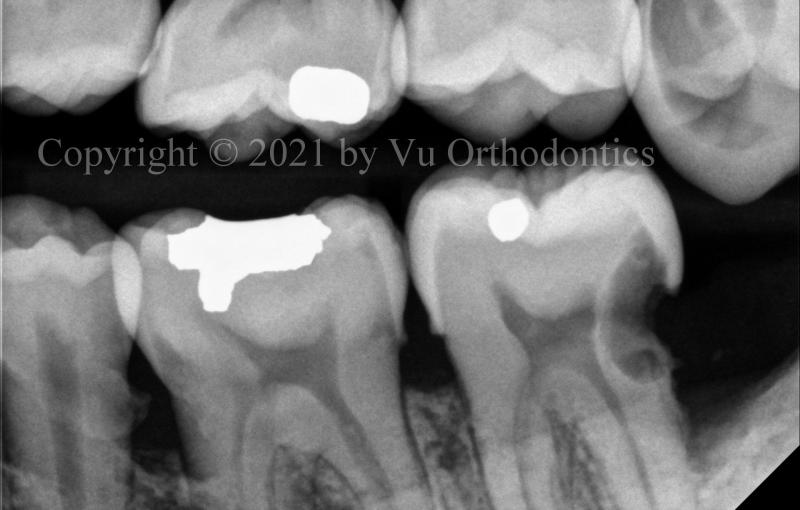

For impacted wisdom teeth, especially on the lower, doing nothing is a bad option. Figure 5 shows the damages to the lower 2nd molars by the corresponding lower wisdom teeth.

(a)

(b)

Fig. 5 Damages to the lower 2nd molars by the wisdom teeth: (a) damaged lower right 2nd molar, (b) damaged lower left 2nd molar.

Another example of damages to the lower 2nd molars by the lower wisdom teeth is shown in Fig. 6.

Fig. 6 Damages to the lower 2nd molars (Teeth #31 & #18) by the wisdom teeth (Teeth #32 & #17): (a) panoramic radiograph, (b) Tooth #31 is the lower right 2nd molar; Tooth #18 is the lower left 2nd molar